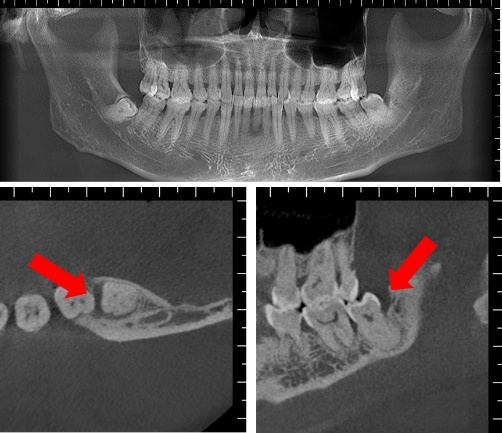

图片1 (1).png

左下阻生智齿

通过口腔专科检查及CBCT检查,发现患者的左下智齿近中阻生,其远中及近中可探及牙周深袋,左下第一磨牙黏膜转折处可见窦道,左上智齿阻生。根据病史及发病部位考虑,这名患者最终被诊断为智齿反复发炎导致的“牙源性皮瘘”。